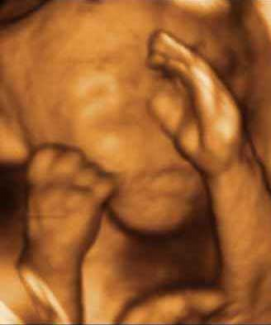

Feto Completo Gemelos Manos Pies Niņa

Manos